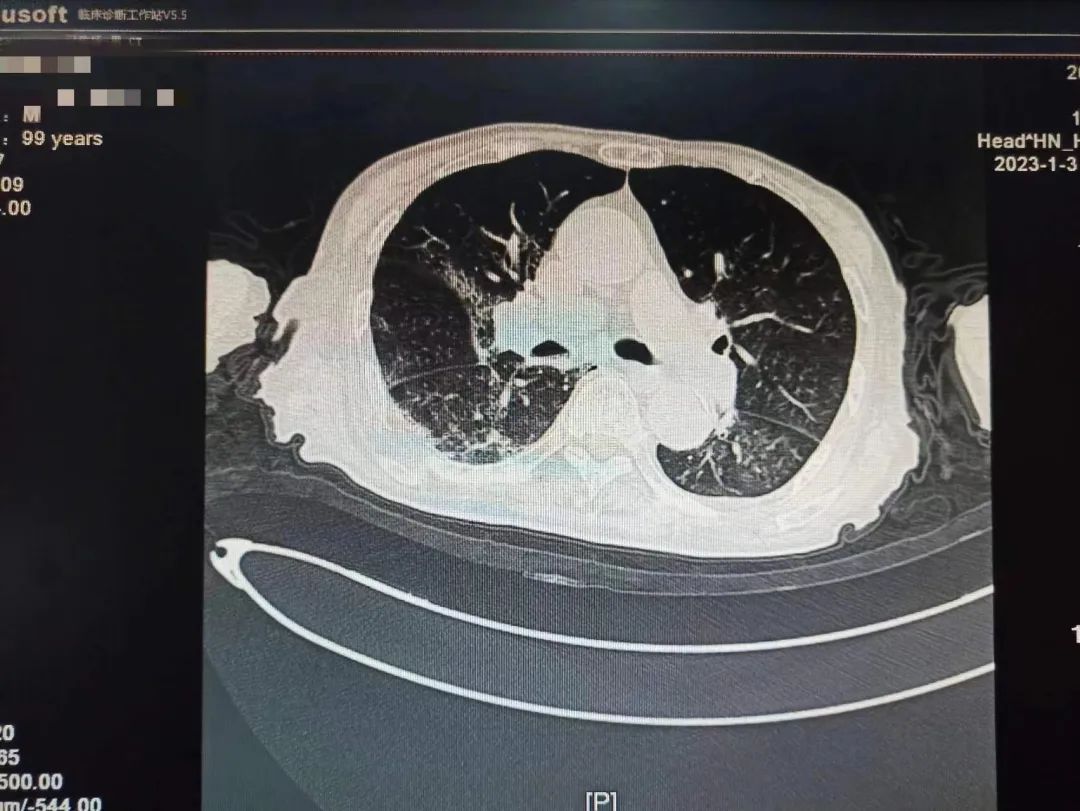

不放弃每一个生命!全力救治!经过连续数日医护团队的精心救治,2023年1月9日,呼吸与危重症医学科医护团队再次对老人病情进行综合评估,检查显示患者肺部病灶明显吸收,精神明显好转,可以正?;疃?,和感染前身体体征一致。出院当天老人握着刘家昌主任的手激动的说:“多亏刘主任了,要不是你和咱们医院医护团队,我这关是闯不过去了,我还以为我过不去这一百岁坎了?!绷跫也魅味岳先撕图沂粝晗附淮顺鲈嚎蹈粗傅家饧白⒁馐孪?。